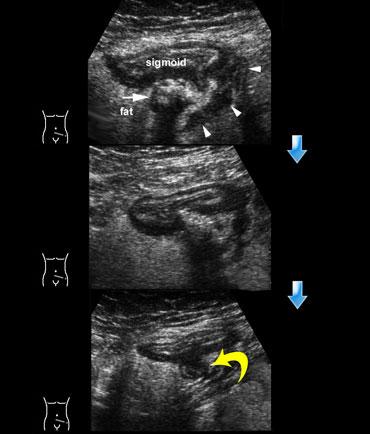

Bên trái là diễn tiến tự nhiên, lành tính của viêm túi thừa đại tràng sigma.

TRÊN: Siêu âm cho thấy dày thành đại tràng sigma tại vị trí túi thừa đang viêm (mũi tên) chứa sỏi phân (giai đoạn 0).

Lưu ý mô tăng âm, không nén được xung quanh đại diện cho mạc nối và mạc treo đang bao bọc hiệu quả vị trí sắp thủng.

Trong lớp mỡ, có thể thấy các dải giảm âm dạng tuyến tính (đầu mũi tên).

GIỮA: Một ngày sau, bệnh nhân cảm thấy khá hơn một chút.

Sỏi phân không còn nhận diện được rõ ràng và nội dung túi thừa đang phình ra phía lòng đại tràng sigma, dấu hiệu của sự thoát dịch sắp xảy ra.

DƯỚI: Hai ngày sau đó, bệnh nhân gần như không còn triệu chứng.

Mủ và chất phân đã thoát hoàn toàn vào lòng đại tràng sigma, để lại một túi thừa rỗng (mũi tên cong).